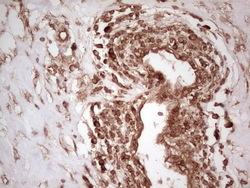

- Submitted by

- OriGene (provider)

- Main image

- Experimental details

- Immunohistochemical staining of paraffin-embedded Carcinoma of Human lung tissue using anti-WIBG mouse monoclonal antibody. (Heat-induced epitope retrieval by 1 mM EDTA in 10mM Tris, pH8.5, 120C for 3min, TA806496)

- Validation comment

- IHC